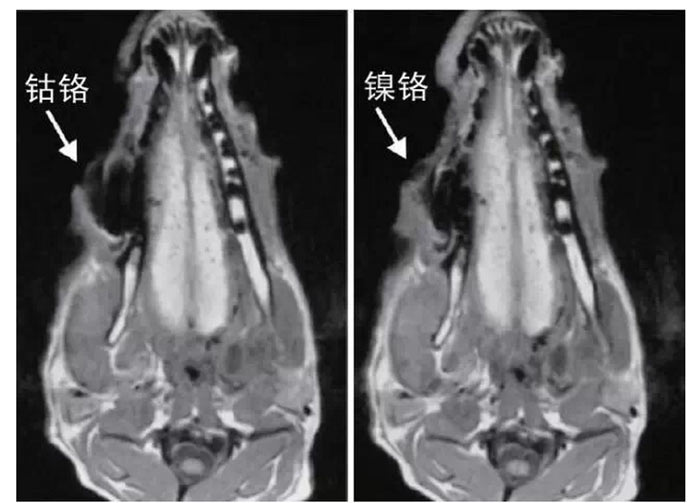

文獻(xiàn)研究中常使用的金屬包括鎳鉻合金、鈷鉻合金、低鈦合金、純鈦、金合金、金鈀合金、銀鈀合金等成分如表所示。大量研究得出近乎一致性的結(jié)論。金合金、金鈀合金、銀鈀合金對MRI影響甚微,與全瓷材料、丙烯酸樹脂極為相似,表現(xiàn)為修復(fù)體影像邊緣光滑、無變形、無偽影;純鈦金屬對MRI影響較小,接近于全瓷材料;但有的研究卻發(fā)現(xiàn)純鈦在核磁共振場中也產(chǎn)生偽影,但偽影涉及的掃描層數(shù)較少;低鈦合金(鈦合金)對MRI影響較大,介于純鈦和鎳鉻合金之間,中度偽影;鎳鉻合金、鈷鉻合金對MRI影響很大,鈷鉻合金更甚;表現(xiàn)為重度偽影、圖像扭曲變形(圖1、圖2)。不難看出,對MRI 影響,全瓷材料、樹脂材料<金合金等貴金屬<純鈦<低鈦合金<鎳鉻合金<鈷鉻合金。有研究發(fā)現(xiàn)鈷鉻合金橋偽影大小與修復(fù)體長軸一致,影響范圍為固定橋近遠(yuǎn)中徑2倍,頰舌徑的4倍;相同外形金屬修復(fù)體厚度增加,偽影增加。單個(gè)金屬樁核偽影可波及到上頜竇、牙槽骨、舌體、舌下腺等組織器官,但對眼底、眼內(nèi)容物、腦組織和頸椎成像基本無影響。

圖2 4種金屬冠在犬MRI檢查中的影響,圖片引自《實(shí)用口腔醫(yī)學(xué)雜志》2014第30期《4種金屬冠對磁共振成像影響的對比研究》一文,作者高嵐等